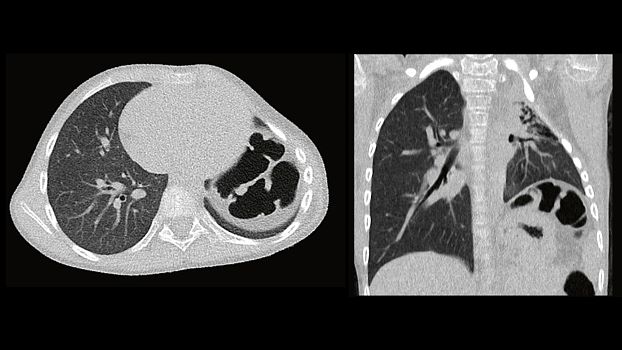

Клинические изображения

SOMATOM go.Up позволяет проводить скрининговые исследования лёгких и толстой кишки, а также исследования сердца для оценки коронарного кальция. Благодаря субмиллиметровой коллимации SOMATOM go.Up обеспечивает высокое пространственное разрешение, тем самым повышая чувствительность диагностики в онкологии.